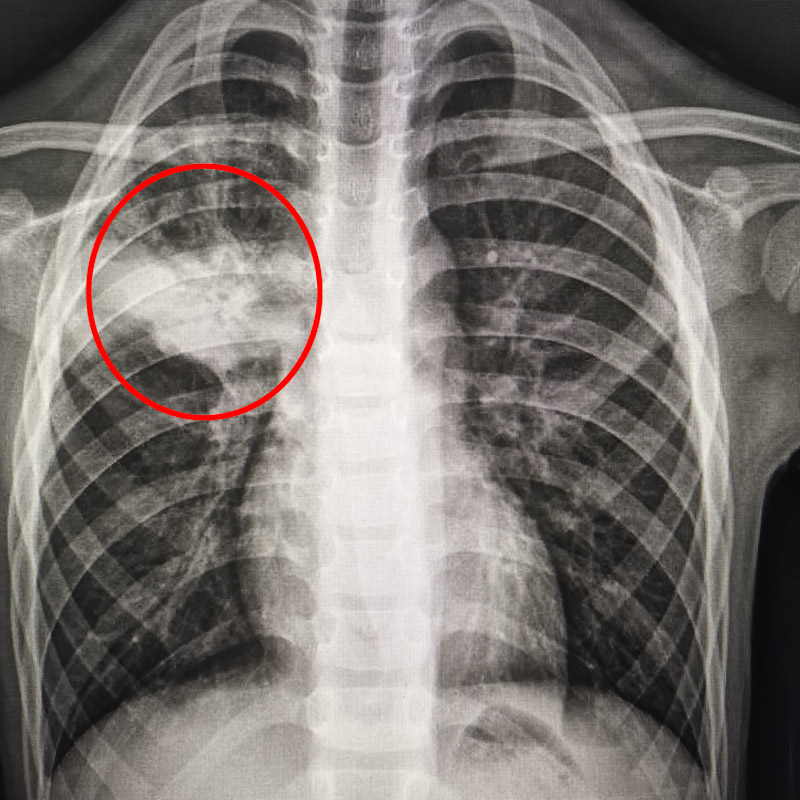

家長(zhǎng)焦急地帶孩子前往柳州市人民醫(yī)院兒科就診。小萱的胸片報(bào)告顯示,她的右上肺出現(xiàn)一大片感染灶。家長(zhǎng)很驚訝,從發(fā)病到檢查出肺部大片感染灶,病程才5天,病情進(jìn)展太快了。

6歲鵬鵬的病情與小萱相似。鵬鵬的媽媽稱,孩子以前發(fā)熱、咳嗽,在家吃一兩次退燒藥就好了。但這次,鵬鵬發(fā)熱4天,吃藥也難以退至正常,且咳嗽劇烈。到醫(yī)院就診后,鵬鵬的檢查報(bào)告顯示,胸部CT也出現(xiàn)左下肺大片感染灶,肺炎支原體IgM抗體也呈陽(yáng)性。